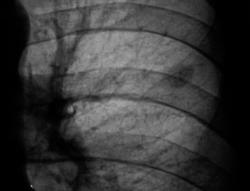

Зафиксировано увеличение тени в размерах. Произведена рентгенография в прямой стандартной проекции.

Было высказано предположение о наличии "маленького периферического рака", зафиксирована "линзеподобная тень" паракостально. Пациент направлен на консультацию в онкологический диспансер.

В дистансере приняли решение о наблюдении в динамике.

Окружающая легочная ткань - 2008 и 2009 г.